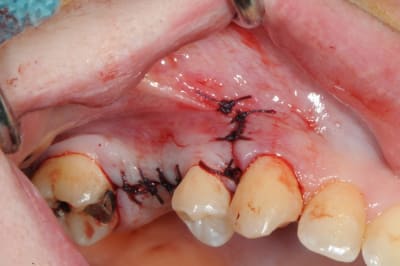

je sais pas si c'est un produit miracle, mais pour les sinus lift, c'est fantastique.

outre le fait de stabiliser un implant dans un sinus type SA4, pas de risque de voir partir le produit comme avec les granules de bioos et autres..

l'autre avantage est de ne pas avoir à mettre de membrane de recouvrement.

je suis donc hyper satisfait du résultat.

jugez plutôt...

l'application type du VitalOs, avec le bone splitting.

Chapeau gamin c'est très propre et très bien iconographié.

le protocole tel qu'il est d'écrit voudrait que l'on applique d'abord une couche de vital os en palatin - laisser durcir - mettre l'implant puis mettre une dernière couche.

ici, j'ai mis l'implant- maintenu la membrane de Schneider en poussant avec l'embout sur celle ci et terminer l'injection du produit. c'est l'un des avantages de ce produit, il est livré avec deux embouts donc les deux solutions sont possibles pour une même seringue.